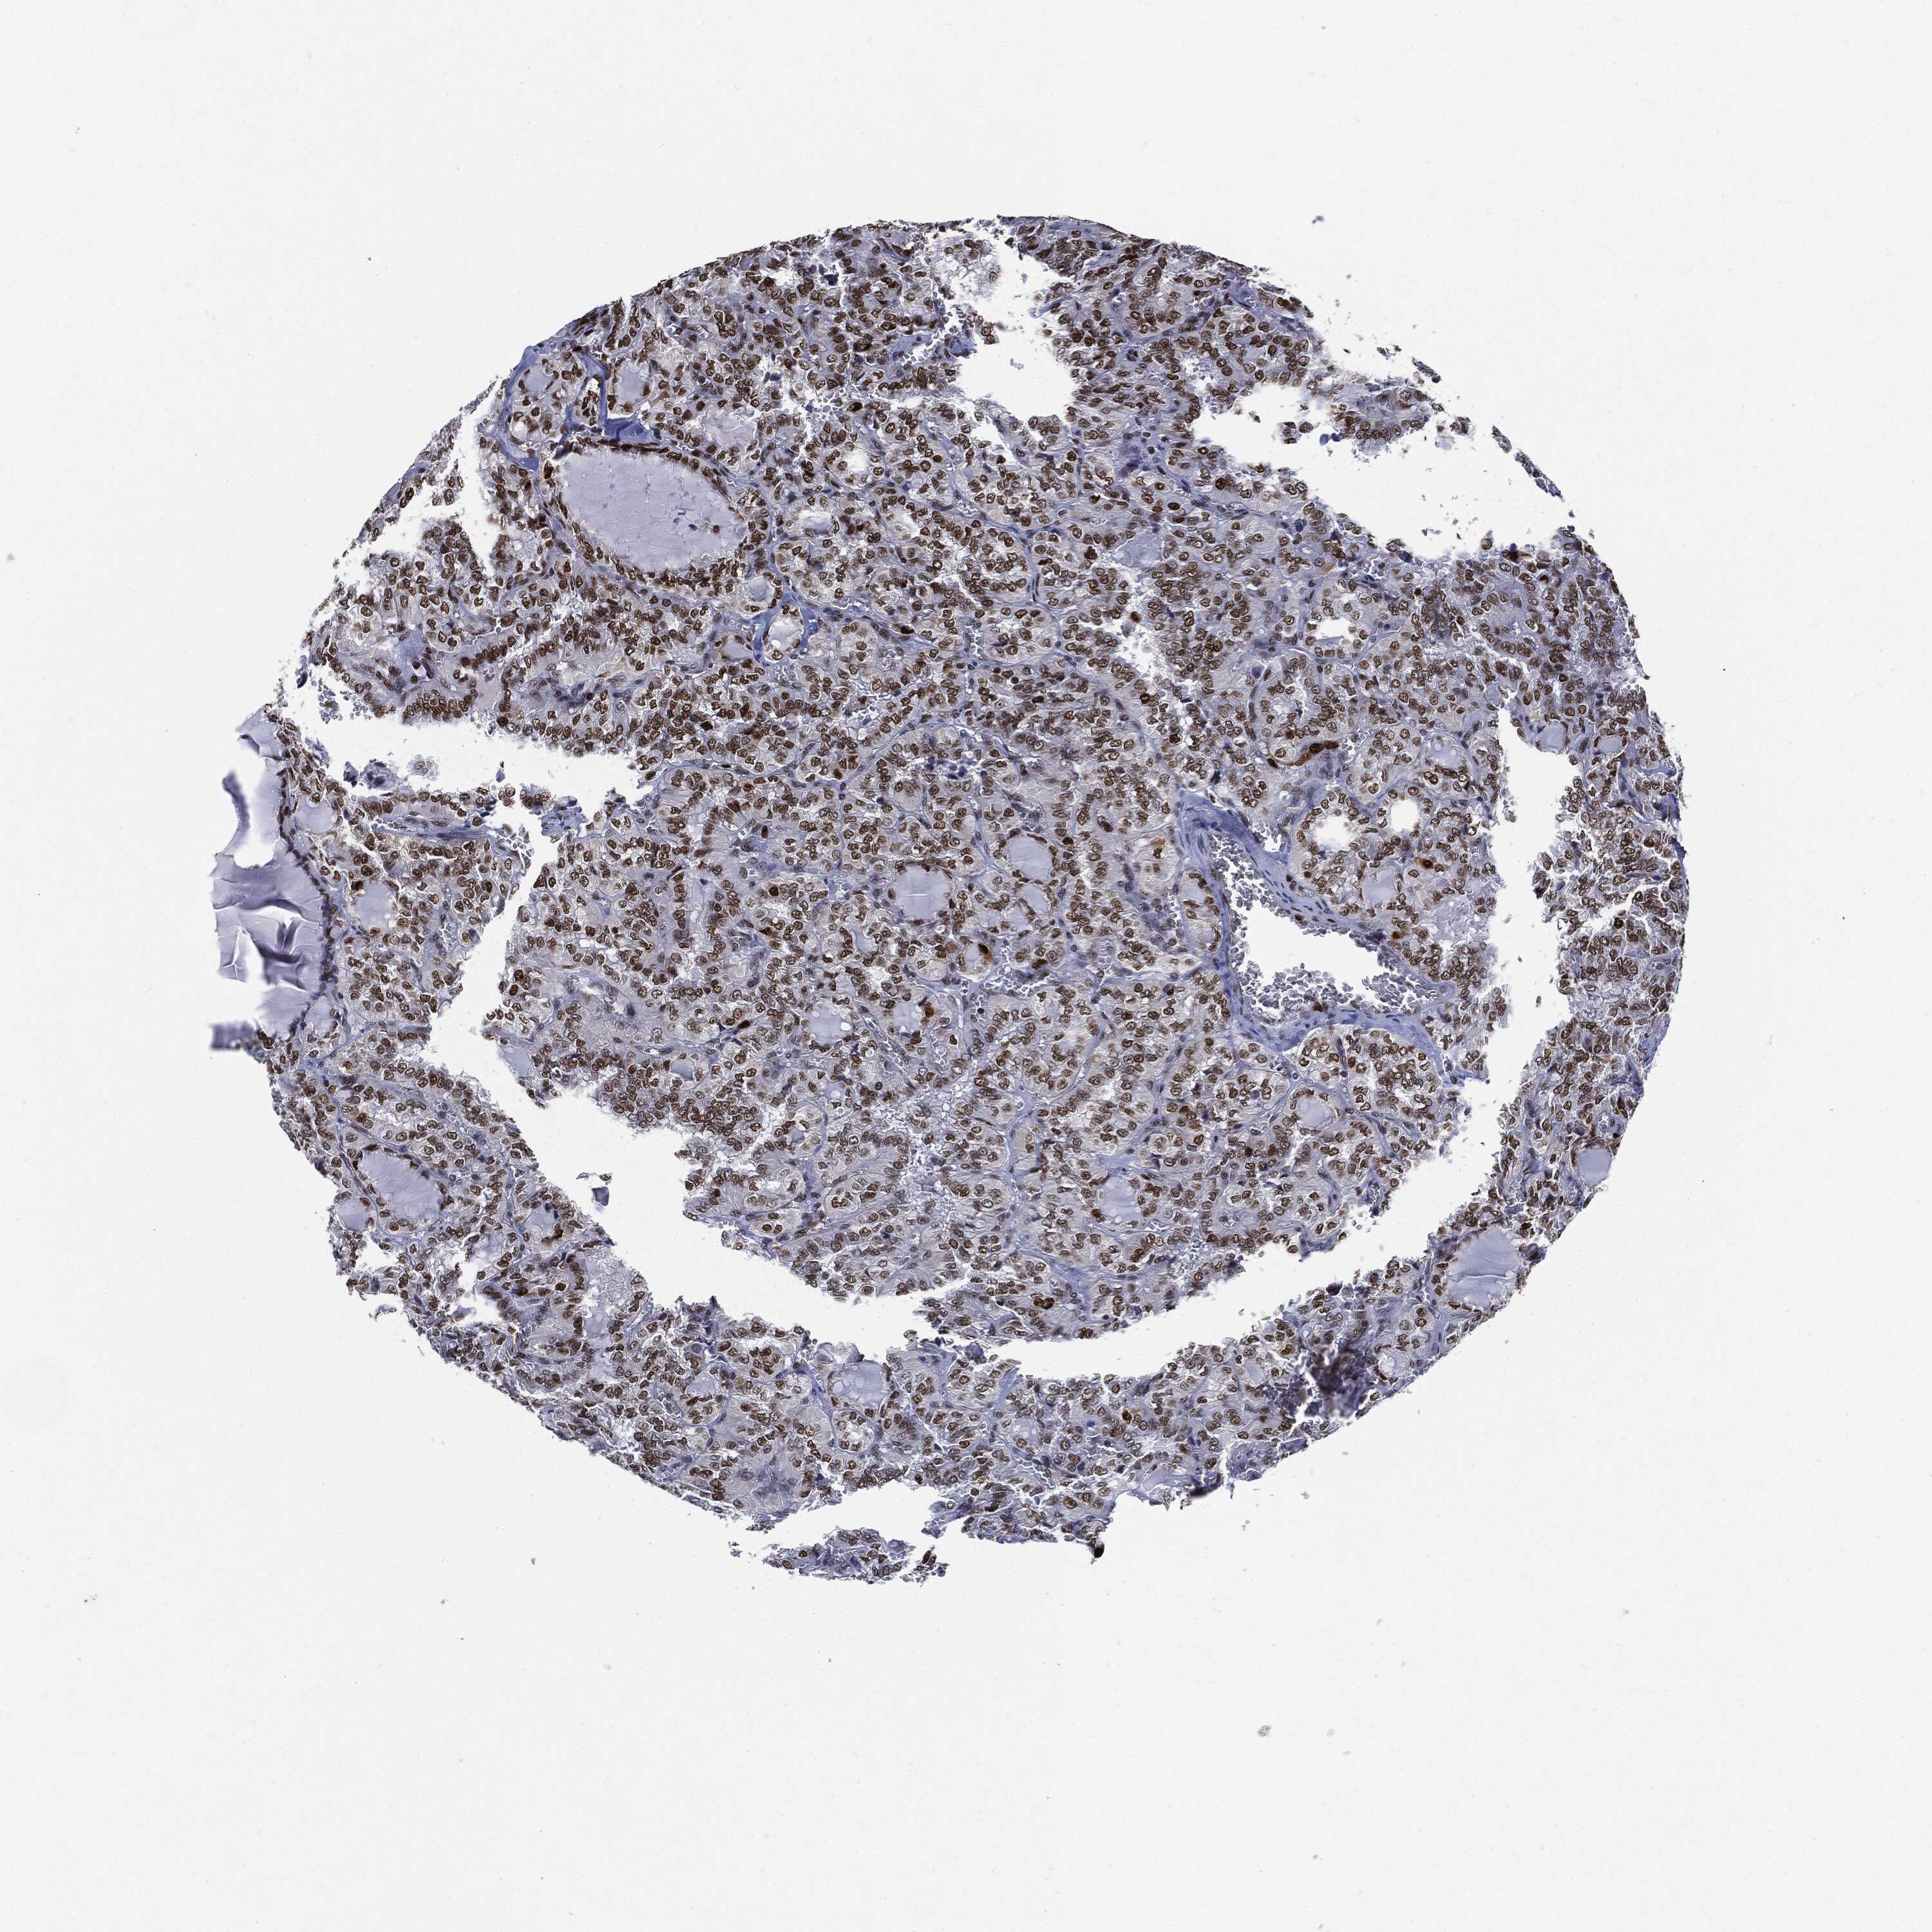

THYROID CANCER - Protein expressioni

A mouse-over function shows sample information and annotation data. Click on an image to view it in a full screen mode. Samples can be filtered based on level of antibody staining by selecting one or several of the following categories: high, medium, low and not detected. The assay and annotation is described here.

Note that samples used for immunohistochemistry by the Human Protein Atlas do not correspond to samples in the TCGA dataset.

Antibody stainingi

Antibody staining in the annotated cell types in the current human tissue is reported as not detected, low, medium, or high, based on conventional immunohistochemistry profiling in selected tissues. This score is based on the combination of the staining intensity and fraction of stained cells.

Each image is clickable and will lead to virtual microscopy that enables deeper exploration of all samples and also displays staining intensity scores, fraction scores and subcellular localization as well as patient and tissue information for each sample.

HPA030521

HPA030522

HPA030523

CAB000148

CAB080240

CAB080241

CAB080242

Staining

High

Medium

Low

Not detected

Intensity

Strong

Moderate

Weak

Negative

Quantity

>75%

75%-25%

<25%

None

Location

Nuclear

Cytoplasmic/membranous

Cytoplasmic/membranous,nuclear

Papillary adenocarcinoma, NOS

Follicular adenoma carcinoma, NOS

Carcinoma, NOS